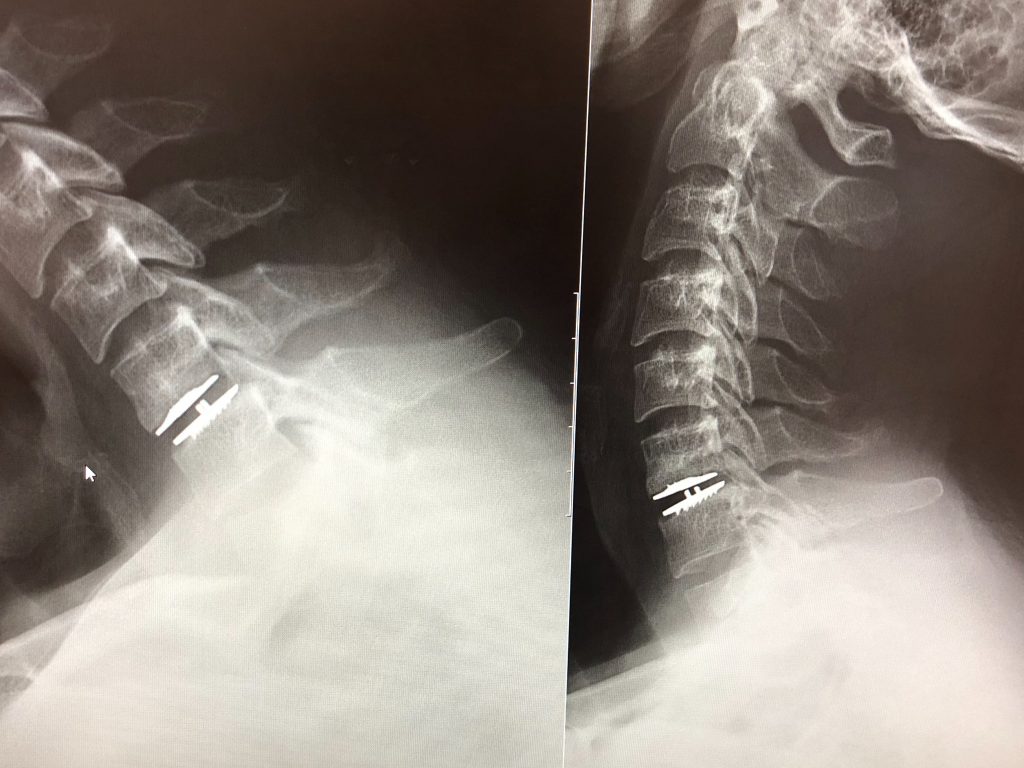

Dr. Huang and his entire staff are incredible. I was having neck pain with numbness and weakness in my left arm due to herniated discs in my neck. After consulting with two other spine surgeons - one recommended a three disc fusion and the other a two disc fusion - I met with Dr. Huang. Dr. Huang takes his time to completely explain what he thinks is the best option for you (the wait is worth it). He answers all your questions and makes sure you are completely comfortable with his recommendations. As a 36-year-old with two young children and an active occupation, I need to maintain my mobility while being completely healed. Dr. Huang recommended a one level disc replacement at the C6-C7 level. I have complete mobility back with no lingering pain or weakness. I would not have the mobility I have now with the fusions. It was great to have an alternative option. I move better now then pre-surgery. I thank Dr. Huang, his entire staff, and HSS for their professionalism and care through my injury.